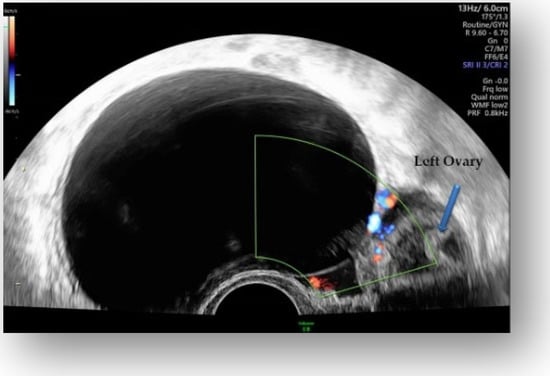

Considering all the information gathered, we first decided to perform an ultrasound (US) which revealed a large hypoechoic cystic formation on the left of the uterus, misdiagnosed as a paraovarian cyst measuring 80 mm (Figure 1, Figure 2, Figure 3 and Figure 4).

Figure 2.

Hypoechoic cystic formation with peripheral doppler flow, without intracystic vegetations.